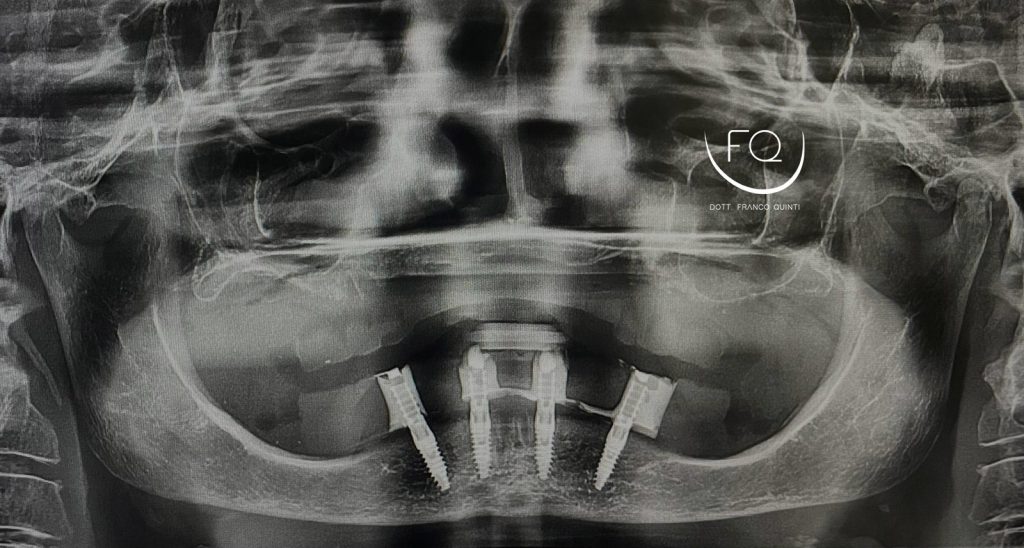

Oggi vi presento un caso di riabilitazione dell’arcata inferiore eseguito con l’utilizzo di dime scomponibili.

Il trattamento ha previsto l’inserimento di 4 impianti Prama Power di Sweden & Martina e la contestuale riabilitazione protesica provvisoria. Tra 3 mesi il caso verrà finalizzato con una protesi definitiva.